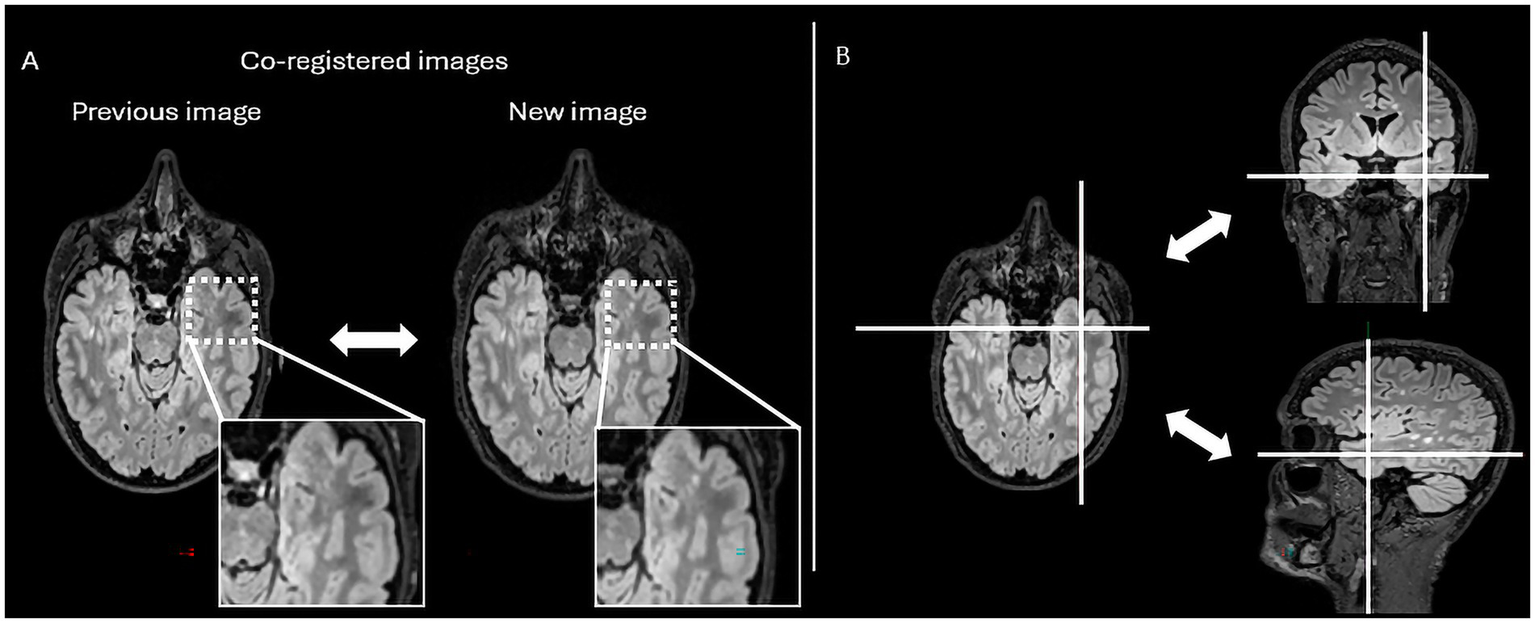

In practical terms, Jazz® enables radiologists to directly compare prior and follow-up scans at the same anatomical location, allowing instantaneous toggling between time points with a single click (mouse or keyboard shortcut). This synchronized display helps the reader identify subtle signal changes. In addition, the software provides a “lesion locking” option: once a lesion is selected, the tool automatically tracks its anatomical location across different time points, ensuring consistent assessment of potential lesion evolution (Figure 1).

Figure 1. The figure represents the reading interface in Jazz® software. It allows a comparison of previous and new MRI FLAIR images of a patient with MS. The reader can easily switch from previous to new image, and vice versa, just by mouse clicking or using a keyboard shortcut (A), while there is as well lesion locking option (B) when the software automatically detects lesion’s anatomical location.

Finally, compared to the ground truth, 61 false positive new lesions were detected by Pixyl.Neuro.MS® software alone, and radiologists did not retain these lesions (Figure 4). False positive lesions were associated with artifacts in 40% (24/61) of cases, while the remaining 60% (38/61) resulted from co-registration errors (28%) and the presence of slowly enlarging lesions (SELs; 26%).

Figure 4. The figure represents a false positive lesion (indicated by the white arrow) which was segmented as a new lesion but actually represents an artifact located at the interface between cerebrospinal fluid and brain parenchyma.